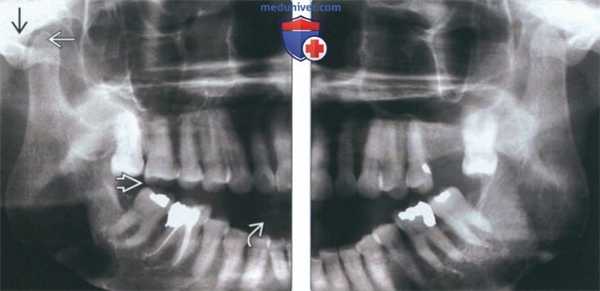

(Слева) На панорамной рентгенограмме у пациента с двухлоронним передним вывихом визуализируется правый мыщелок, смещенный кпереди и кверху относительно сулавного возвышения. Обратите внимание на явный передний открытый прикус, в то время как моляры находятся в окклюзии.

(Справа) На панорамной рентгенограмме у этого же пациента определяются аналогичные изменения слева. Открытый прикус обусловлен неправильным передним положением мыщелка, контакт задних зубов - его верхним положением.